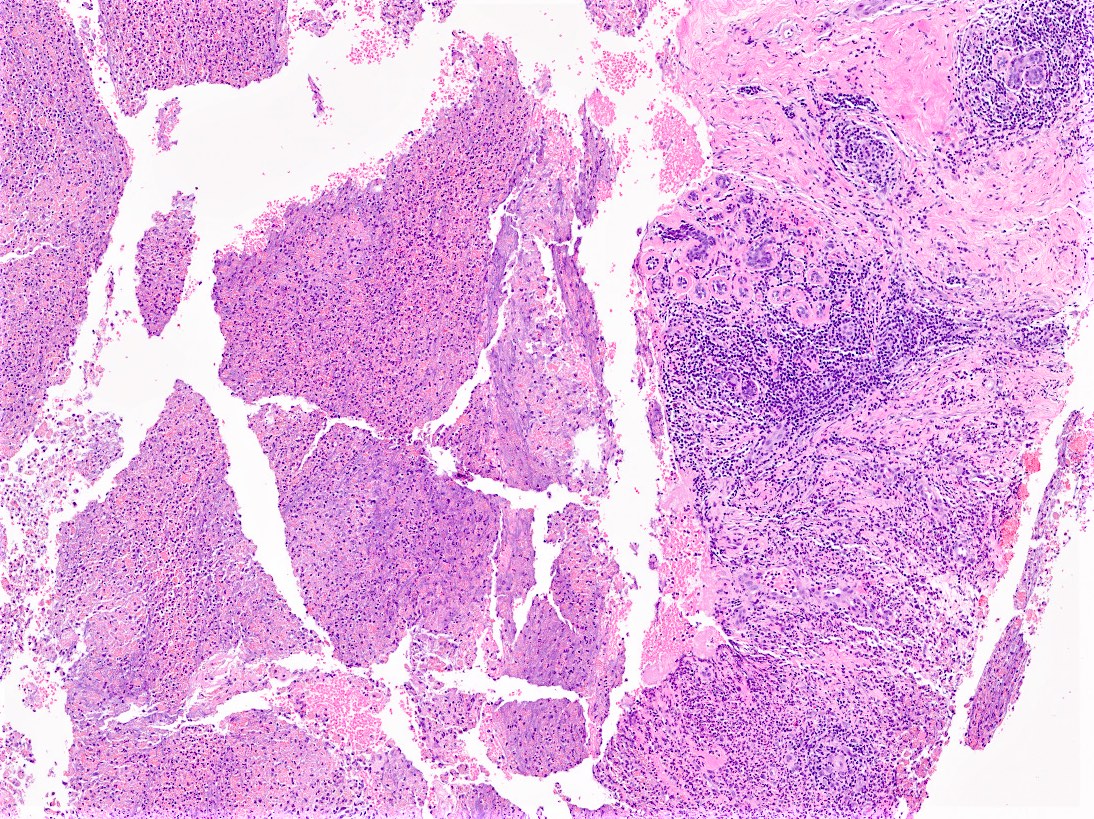

Microscopic (histologic) description

- Mixed dense inflammatory infiltrate, predominantly neutrophils, in breast tissue

- May obscure underlying normal breast tissue

- Tissue necrosis may be present

- Gram stain for microorganisms may reveal bacterial forms (gram positive cocci) associated with neutrophilic infiltrate

- Granulation tissue and chronic inflammation with resolution

- Lymphocytes, giant cells and granulomas are not typical (J Pathol Transl Med 2015;49:279)

Microscopic (histologic) images

Contributed by Kristen E. Muller, D.O.

Contributed by Ayesha Farooq, M.B.B.S. and Julie Jorns, M.D. (Case #515)